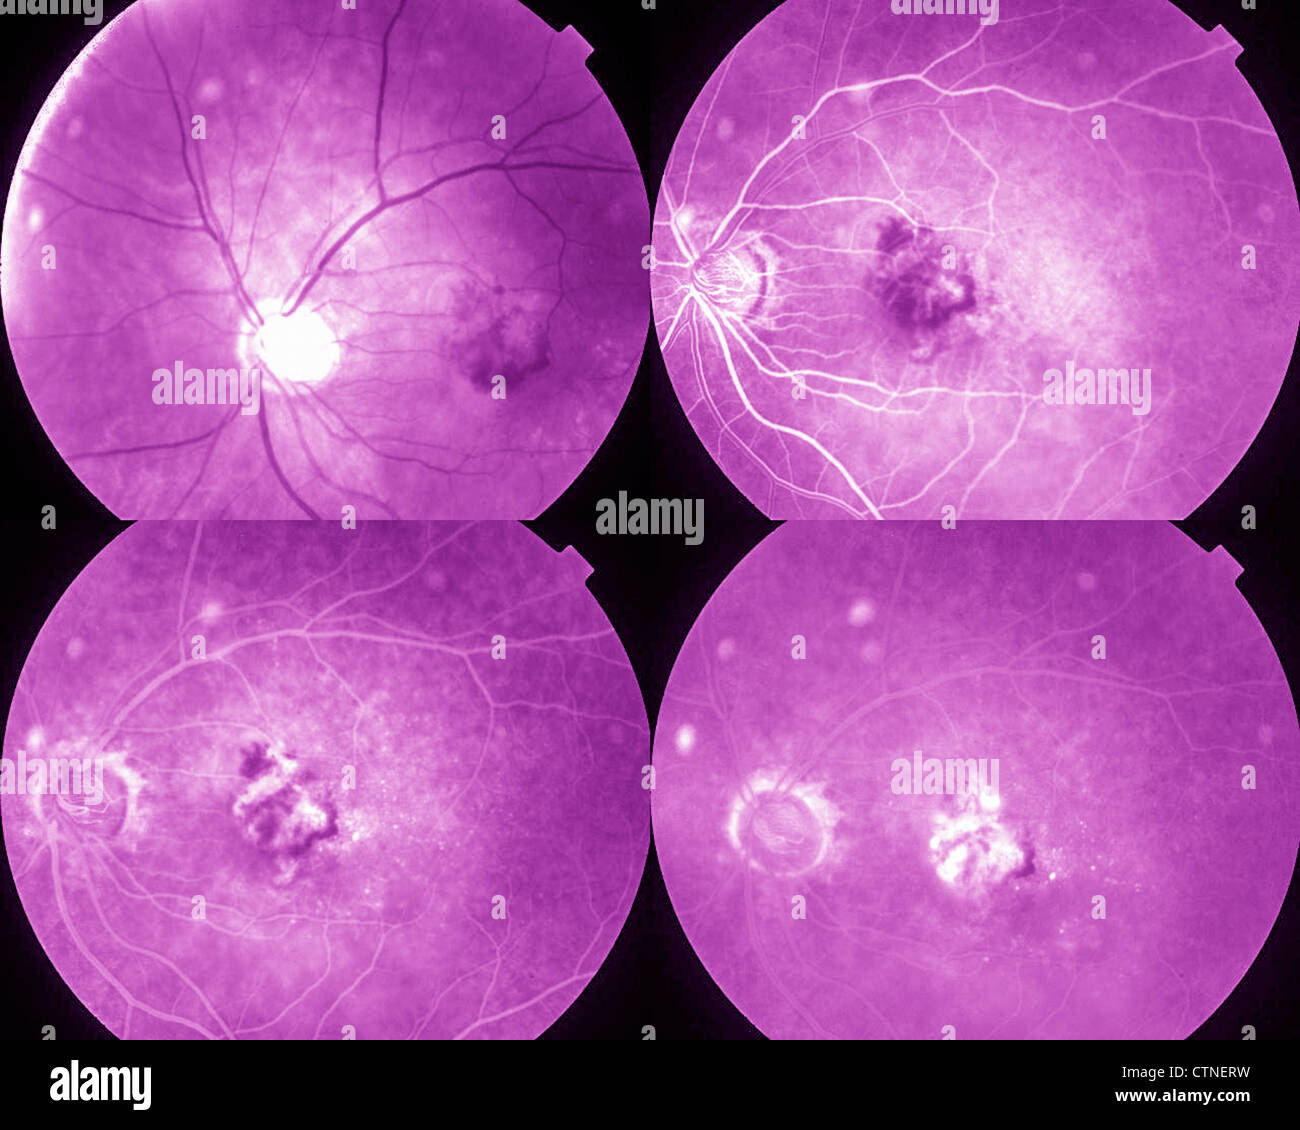

Four phases eye angiography showing AMD age-related macular degeneration Stock Photohttps://www.alamy.com/image-license-details/?v=1https://www.alamy.com/stock-photo-four-phases-eye-angiography-showing-amd-age-related-macular-degeneration-49645117.html

Four phases eye angiography showing AMD age-related macular degeneration Stock Photohttps://www.alamy.com/image-license-details/?v=1https://www.alamy.com/stock-photo-four-phases-eye-angiography-showing-amd-age-related-macular-degeneration-49645117.htmlRMCTNERW–Four phases eye angiography showing AMD age-related macular degeneration

Four phases eye angiogram Stock Photohttps://www.alamy.com/image-license-details/?v=1https://www.alamy.com/stock-photo-four-phases-eye-angiogram-49645115.html

Four phases eye angiogram Stock Photohttps://www.alamy.com/image-license-details/?v=1https://www.alamy.com/stock-photo-four-phases-eye-angiogram-49645115.htmlRMCTNERR–Four phases eye angiogram